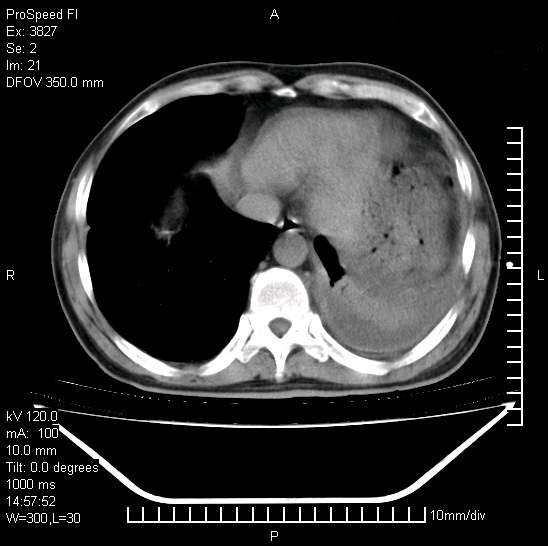

男性,一月前出现右侧肋区疼痛,较剧烈,干咳,无发热,自诉使用抗炎药后缓解,几天前又出现左侧剧烈疼痛,

发热,体温38。9,今天ct,考虑左侧包裹性脓胸,胸腔积液,右上中肺小斑片影,结核/炎症?胸水未见恶性细胞。